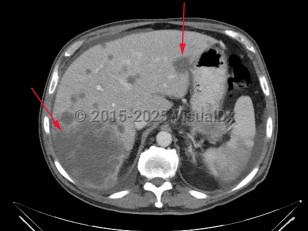

Imaging Studies image of Liver cancer - imageId=7884783. Click to open in gallery.  caption: '<span>Large low attenuation lesion in  the right lobe of the liver as well as several other smaller low  attenuation lesions consistent with metastatic disease to the liver.</span>'

Large low attenuation lesion in the right lobe of the liver as well as several other smaller low attenuation lesions consistent with metastatic disease to the liver.